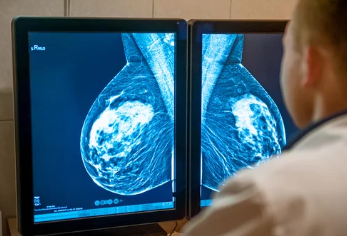

**유방촬영(맘모그라피, Mammography)**은 유방암을 조기에 발견할 수 있는 가장 기본적인 검사 중 하나입니다.

국가건강검진 또는 자가 검사 이후 병원에서 시행하는 이 유방촬영은 촬영 자체뿐 아니라 ‘판독 결과’를 정확히 이해하는 것이 중요합니다.

유방촬영술은 유방 내 조직 변화를 엑스레이를 통해 관찰하는 검사로,

- 유방암을 조기에 발견하기 위한 목적

- 혹, 석회화, 종괴, 조직 밀도 등을 확인